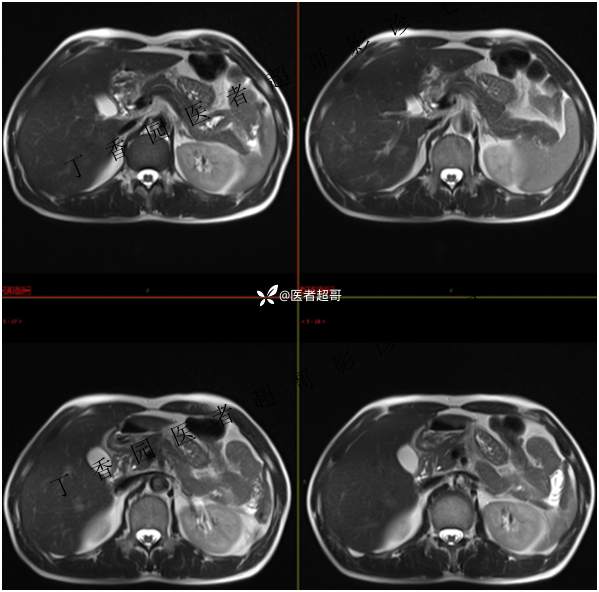

肝胃间隙肿瘤,间质瘤?平滑肌瘤?还是鞘瘤?有结果,请分析!

现病史:患者于3天前查体行肝胆脾胰肾彩超示肝内实性占位,无恶心、呕吐,无发热、寒战,无腹胀、腹泻,进一步于医院行上腹部CT增强示:肝胃交界处肿块。未行特殊治疗。今患者为求进一步治疗,来我院就诊,门诊以“肝占位性病变”收入院。患者自发病以来,神志清,精神可,饮食睡眠可,二便可,体重近期未见明显变化。